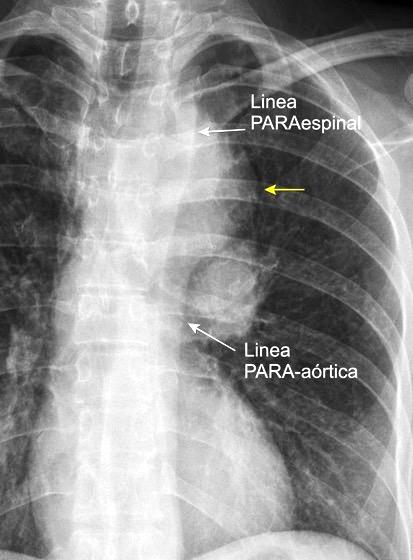

62. LÍNEAS PARAESPINALES. DESPLAZAMIENTO BILATERAL DE

64. LÍNEA PARAESPINAL. DESPLAZAMIENTO UNILATERAL DE